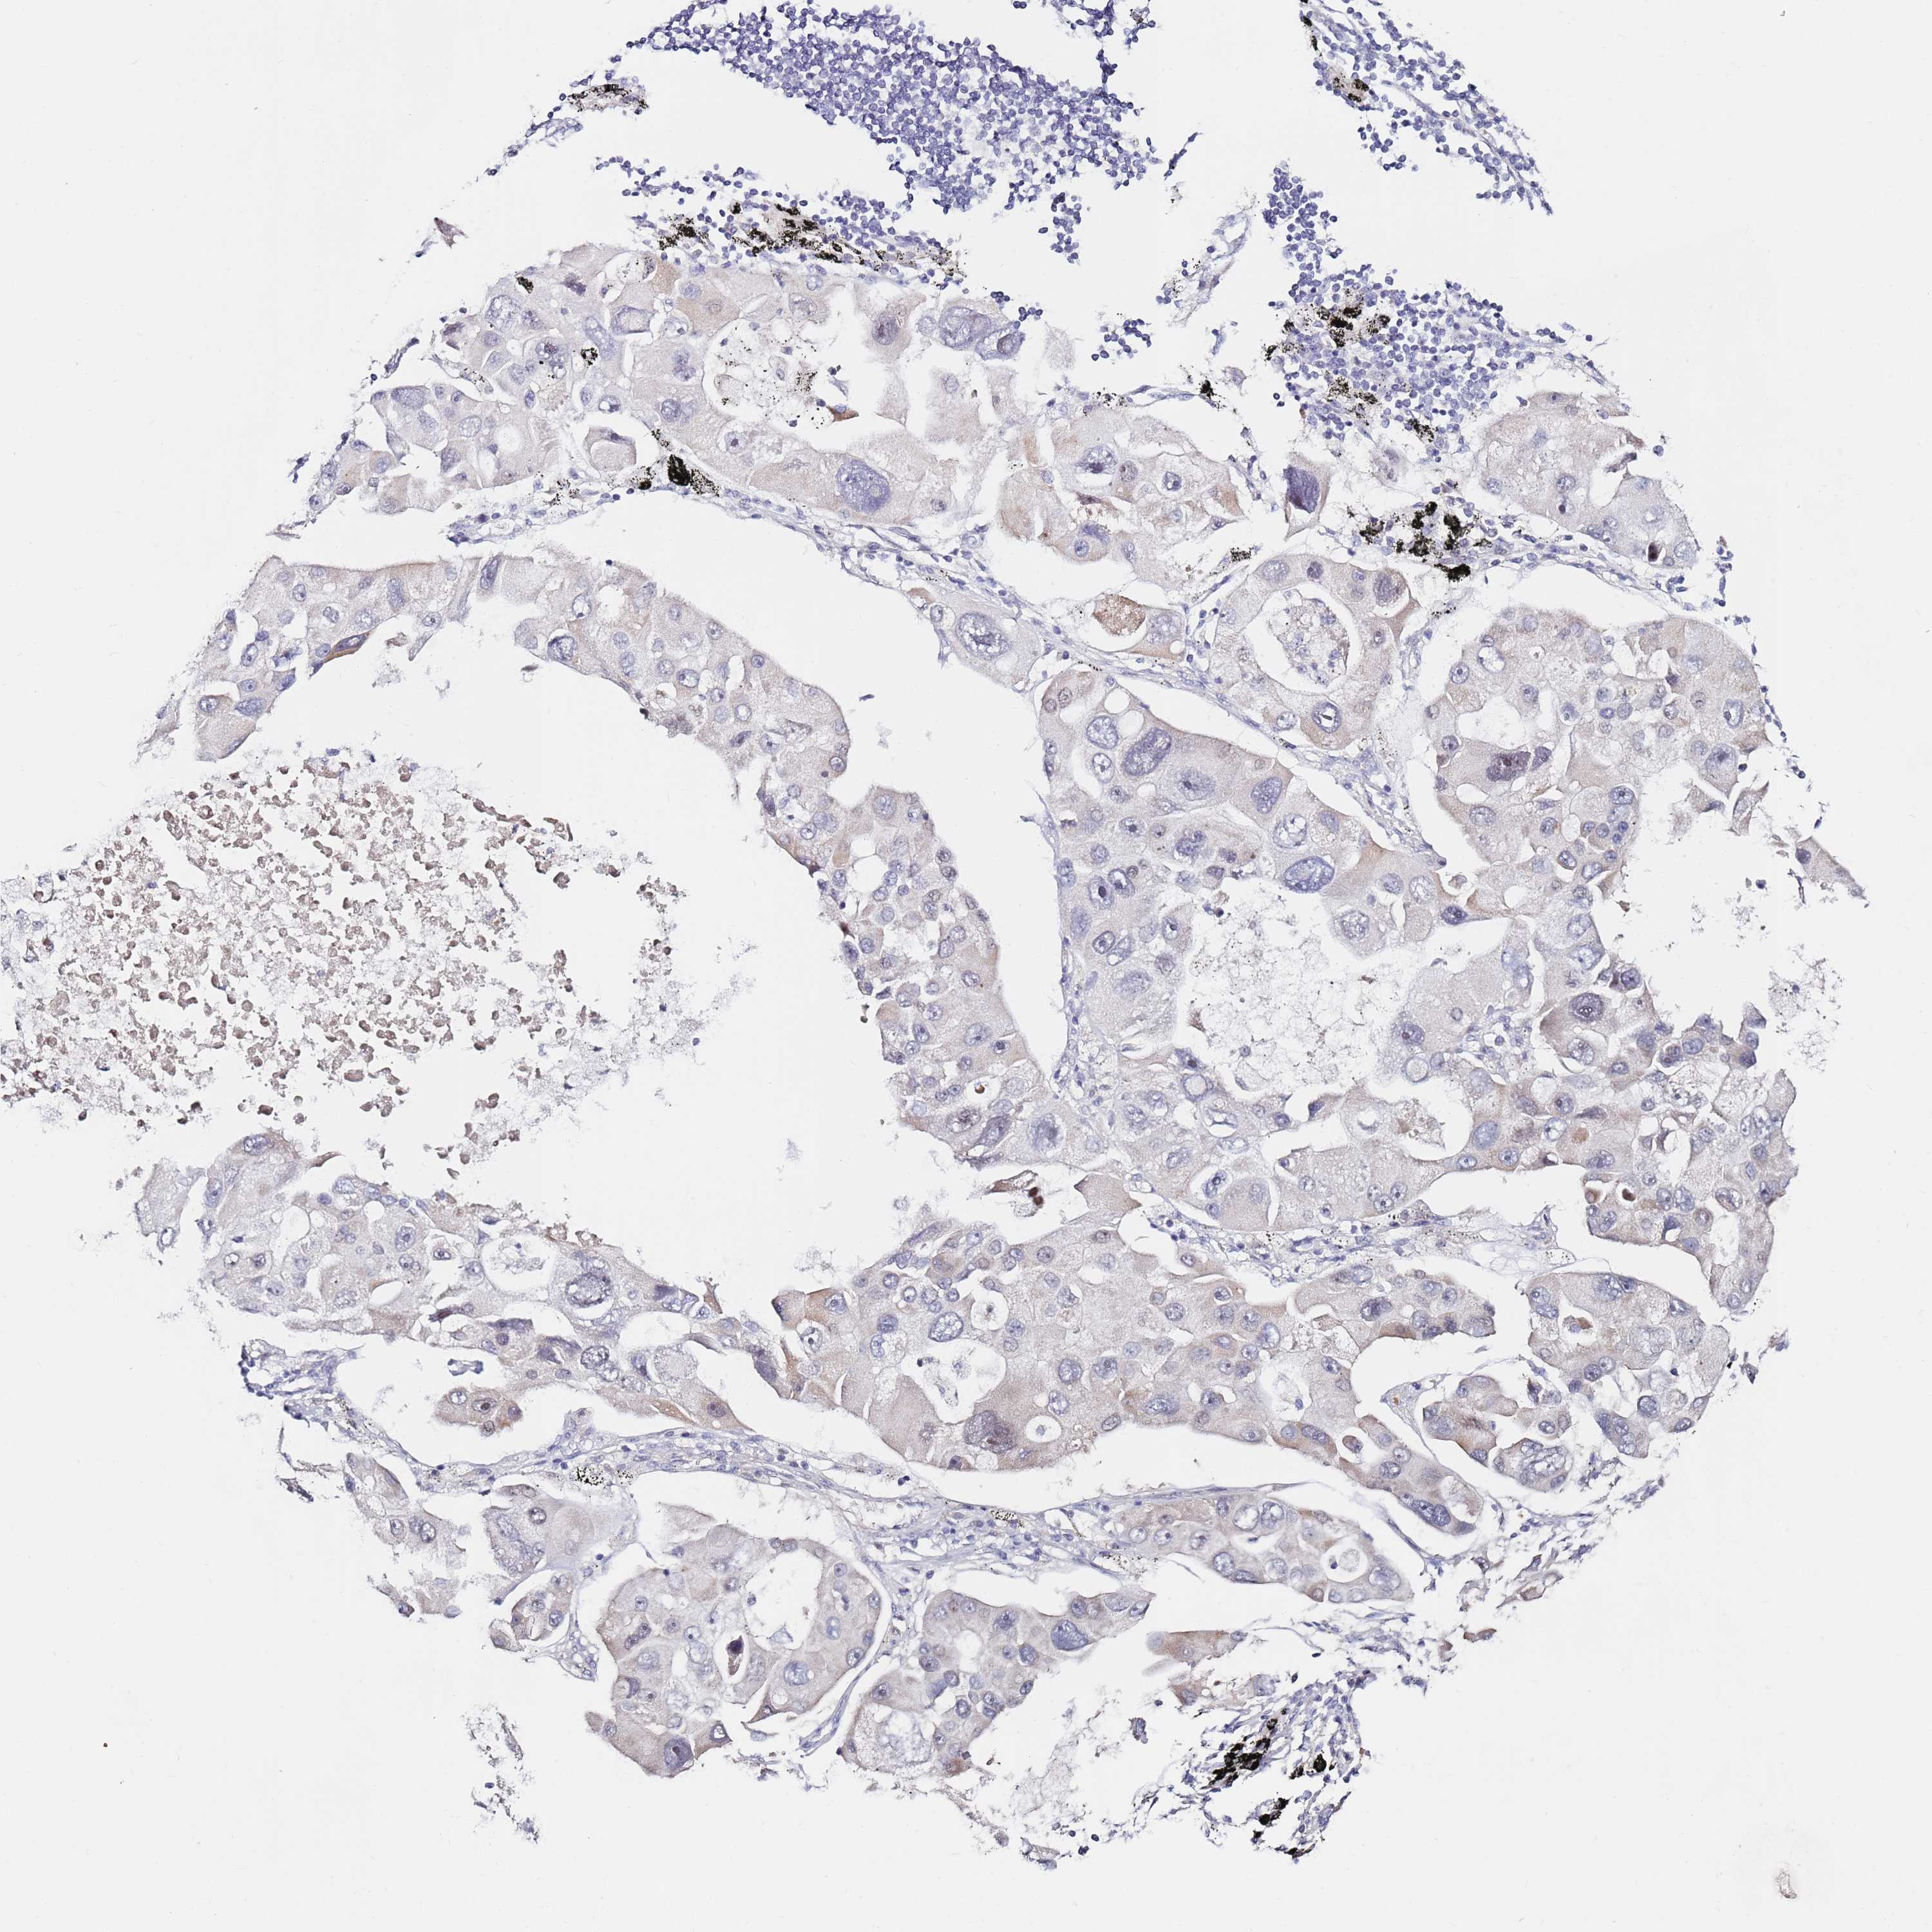

CANCER LUNG CANCER Show tissue menu

LUAD TCGA LUAD VALIDATION LUSC TCGA LUSC VALIDATION PROTEIN LUAD CPTAC PROTEIN LUSC CPTAC PROTEIN EXPRESSION

ANTIBODIES

AND

VALIDATION